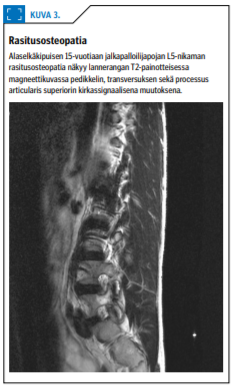

Spondylolyysin tavallisin aiheuttaja on toistuva mekaaninen rasitus, joka johtaa useimmiten alimman lannenikaman takarakenteiden rasitusosteopatiaan (kuva 3 «»5). Mikäli liikuntaa jatketaan, kehittyy rasitusmurtuma (spondylolyysi). Tyypillinen potilas on yli 10-vuotias liikunnallisesti aktiivinen lapsi, jolla on rasitukseen liittyvää alaselkäkipua ja "kireät takareidet".

Kliinisenä löydöksenä voidaan todeta L5-nikaman okahaarakkeen palpaatioarkuus. Laséguen testissä alaraaja ei välttämättä nouse yli 60 asteen. Rasitusosteopatia ei näy natiiviröntgenkuvissa, mutta magneettikuvassa se näkyy lannenikaman hohkaluun turvotuksena (kuva 3 «»5). Murtuma-asteelle edennyt spondylolyysi näkyy myös natiivikuvissa.